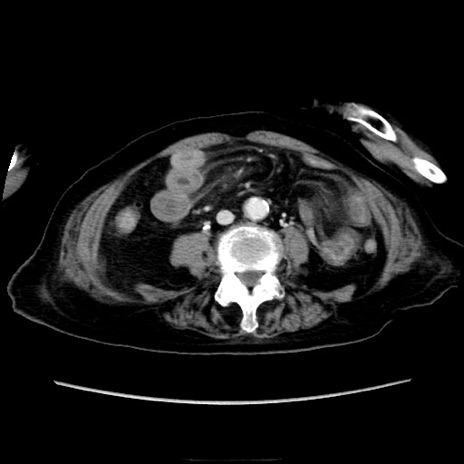

症例40(横断像)

横断像